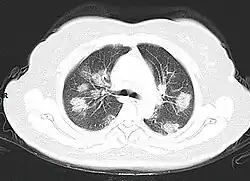

From the CT scans of COVID-19 infected lungs, white patches were observed containing fluid known as ground-glass opacity (GGO) or simply ground glass.[130] This tended to correlate with the clear jelly liquid found in lung autopsies of people who died of COVID-19. One possibility addressed in medical research is that hyuralonic acid (HA) could be the leading factor for this observation of the clear jelly liquid found in the lungs, in what could be hyuralonic storm, in conjunction with cytokine storm.[131]

Imaging

Chest CT scans may be helpful to diagnose COVID‑19 in individuals with a high clinical suspicion of infection but are not recommended for routine screening.[175][187] Bilateral multilobar ground-glass opacities with a peripheral, asymmetric, and posterior distribution are common in early infection.[175][188] Subpleural dominance, crazy paving (lobular septal thickening with variable alveolar filling), and consolidation may appear as the disease progresses.[175][189] Characteristic imaging features on chest radiographs and computed tomography (CT) of people who are symptomatic include asymmetric peripheral ground-glass opacities without pleural effusions.[190]